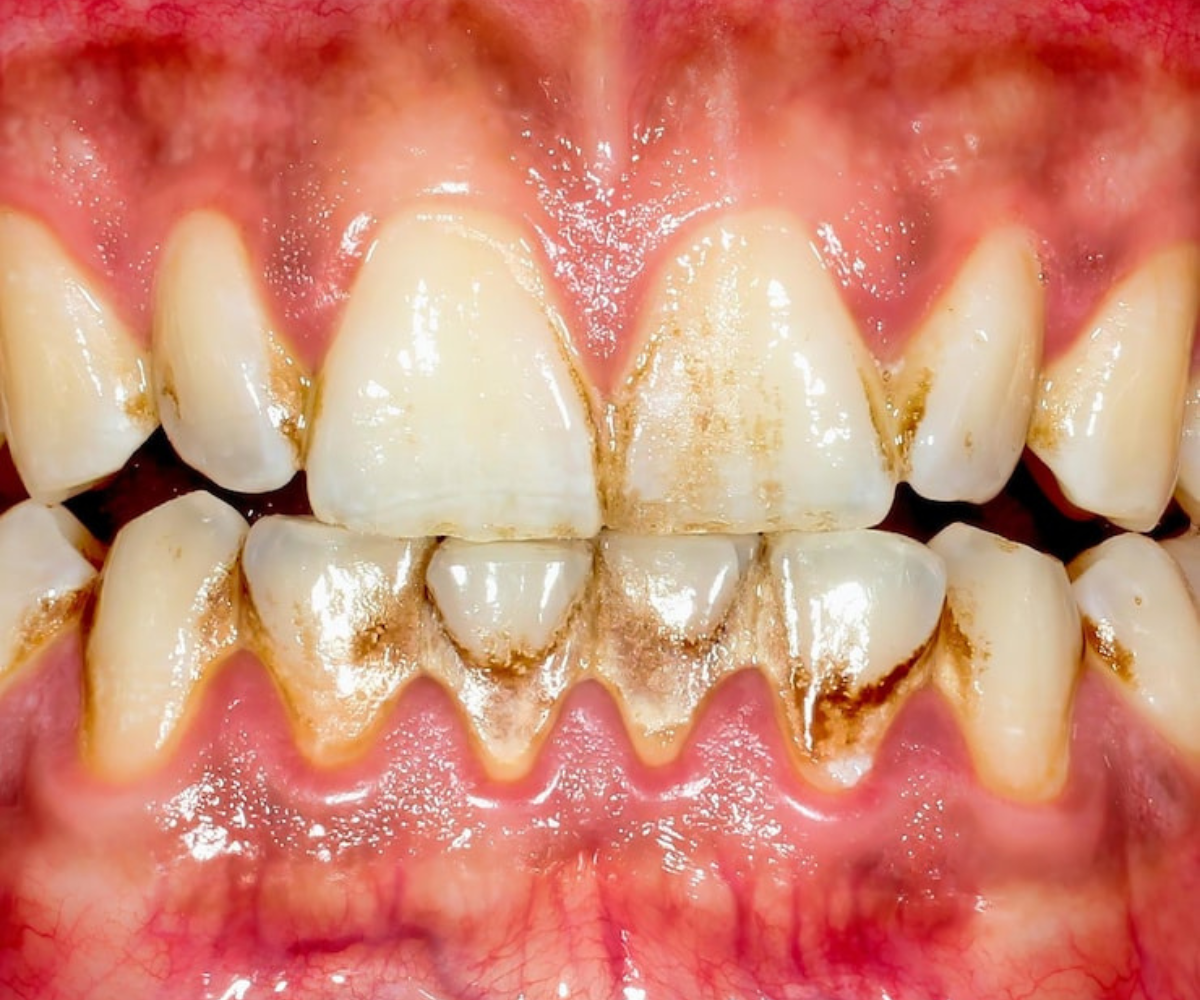

Chromogenic bacteria are oral microbes that produce pigmented metabolites—most often black,

brown, or green pigments—when they metabolize dietary iron, sulfides, or other substrates. The

pigments can bind to the enamel surface, dental plaque, and even the gingival tissues, creating a

characteristic discoloration that is sometimes called “black stain” or “chromogenic staining.”

- Visible staining – The pigments adhere to the pellicle and plaque, producing a dark, often uneven coloration on the labial surfaces of anterior teeth and, less frequently, on posterior teeth.

- Plaque retention – Pigmented biofilm can be more tenacious, encouraging further plaque accumulation and increasing the risk of gingivitis or early periodontal breakdown.

- Aesthetic concerns – Patients frequently seek treatment for the cosmetic impact, especially when the staining is extensive or involves the smile zone.

- Potential link to disease – While the staining itself is not pathogenic, the bacteria that produce the pigments are often associated with periodontal disease and cariespromoting biofilms.